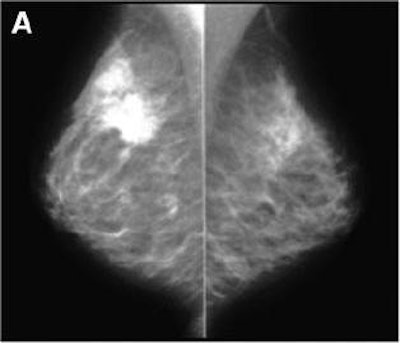

| Above, x-ray mammogram, profile views. Polycystic dysplasia of both breasts. On left, suspicious lesion in supra-areolar region of right breast, corresponding to ductal carcinoma on FNA. On right, left breast is dense, especially in superoexternal part of gland. Multiple cysts are seen with ultrasound but no suggestive lesion was evident. |